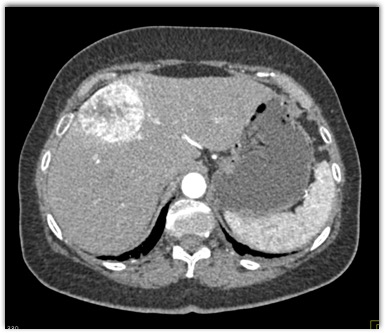

The most likely diagnosis in this case is

FNH

hepatic adenoma

hemangioma

hepatoma